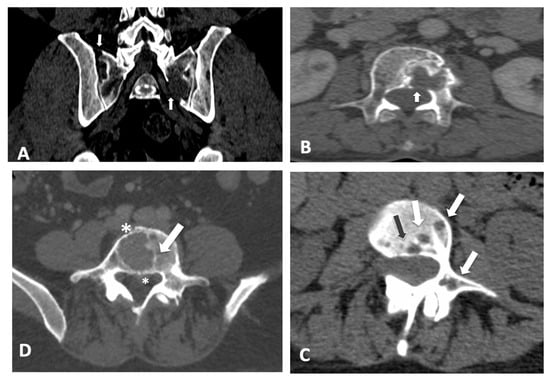

2.2. CT Imaging Atlas

3.1. CT Imaging Atlas